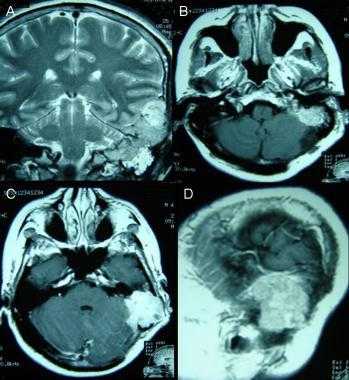

Атипичная с деструкцией пирамиды височной кости. На корональном Т2-взвешенном и контрастированном Т1-взвешенном МР-изображении виден быстрый рост конвекситального объемного образования в сторону намета мозжечка и пирамиды височной кости.